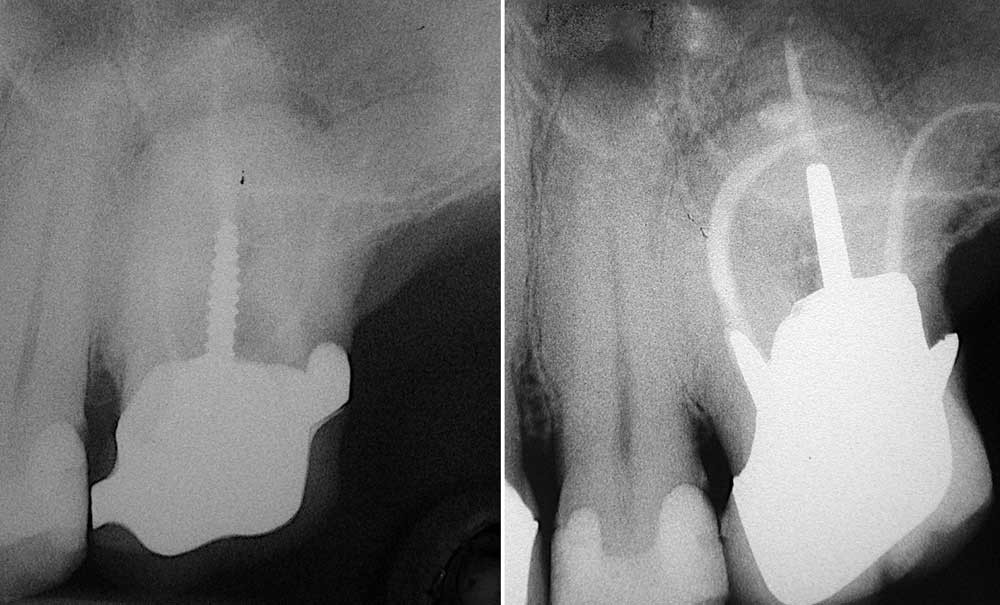

Une méta-analyse publiée en 2021 rapporte qu’un adulte sur deux dans le monde présente au moins une dent avec une parodontite apicale (PA) : cela en fait un véritable problème de santé publique [2]. Les PA apparaissent plus fréquemment associées à des dents préalablement traitées endodontiquement qu’à des dents non traitées, ce qui corrobore les résultats d’études épidémiologiques françaises : 70 à 80 % des traitements endodontiques réalisés en pratique généraliste sont considérés comme inadéquats sur la base d’évaluation radiographique pour une prévalence de PA de l’ordre de 30 à 40 % [4-6]. Parmi les raisons multifactorielles expliquant ces échecs, la complexité technique de l’acte endodontique doit être mise en exergue. C’est pourquoi le praticien généraliste (PG) doit se poser la question des limites de sa pratique de l’endodontie.

L’anticipation du niveau de difficulté présumé de l’acte est un élément déterminant de la prise en charge en endodontie. Que la thérapeutique indiquée soit un traitement endodontique initial ou un retraitement endodontique (orthograde ou rétrograde), une analyse minutieuse de la situation doit être conduite avant le geste.

Un certain nombre de critères cliniques et radiologiques objectifs sont susceptibles d’induire des difficultés opérationnelles :

Courbures canalaires, dents minéralisées/oblitérées ou apparaissant comme telles, anatomies canalaires atypiques, canaux surnuméraires, apex immatures…

Dent préalablement traitée endodontiquement, gestion des traumas, gestion des thérapeutiques…